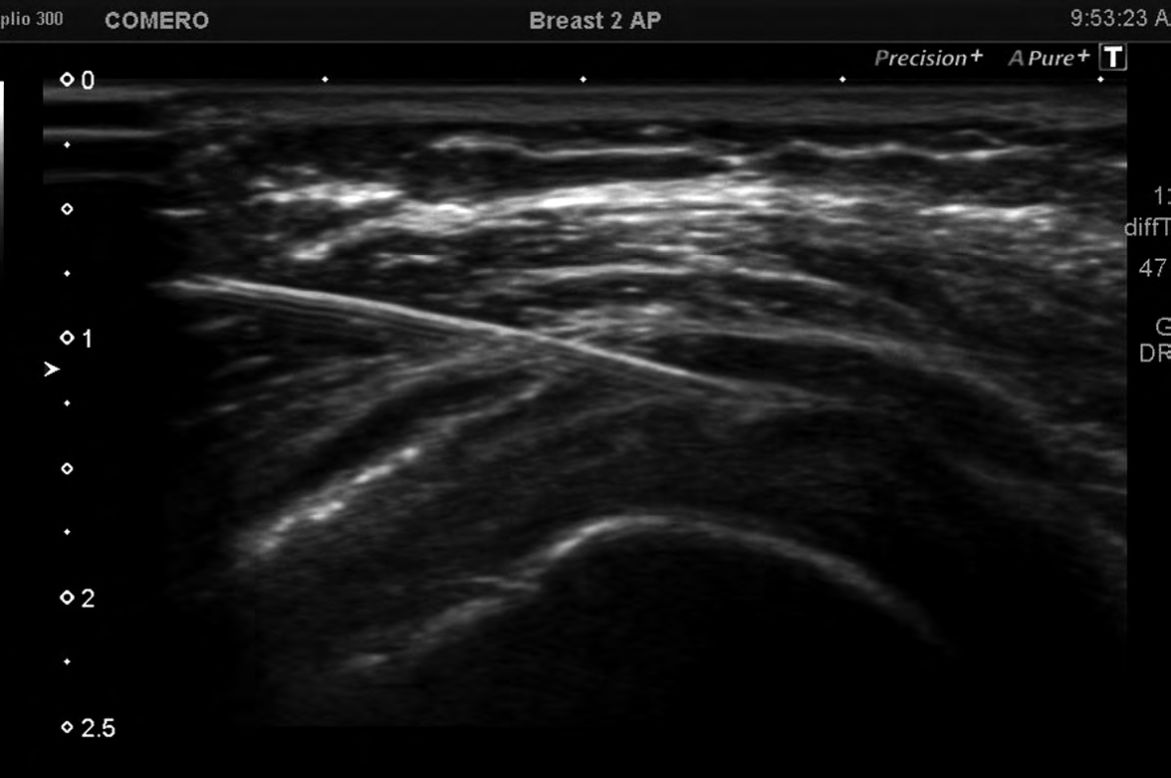

Foto 4 y 5

Aspiración de bursitis SASD se observa punta de la aguja dentro de la bursa, obteniéndose 10cc de líquido. Una vez aspirado se administraron los fármacos

Cuando la bursa SASD no está distendida, es un espacio virtual.

Es así que se debe introducir la aguja muy despacio, e ir inyectando de a pequeñas cantidades hasta alcanzar esta “línea” formada por la interfase deltoides/supraespinoso. Cuando efectivamente se está en el lugar indicado, se forma una lámina líquida, que va desplegando esta interfase a medida que se inyectan los fármacos. Dada la precisión que requiere esta maniobra, pensamos que una maniobra a ciegas en la inmensa mayoría de las veces infiltrará o bien al músculo deltoides, o al tendón del supraespinoso.